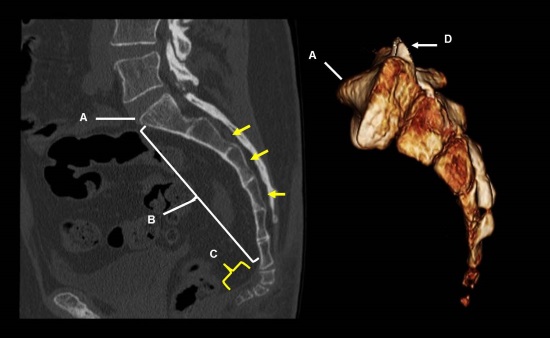

Травмы копчика

Перелом копчика происходит довольно редко, обычно во время серьезных дорожно-транспортных происшествий при ударе. В момент травмирования боль острая, пронизывающая, вызывающая помутнение сознания. На реабилитационном этапе ее интенсивность существенно снижается, но дискомфорт в нижней части спины ощущается еще несколько месяцев, особенно при ОРВИ, рецидивах хронических патологий, смене климатических поясов.

Так как боль в копчике у мужчин может возникать по множеству причин, то требуется проведение дифференциальной диагностики. Поэтому пациенту назначается ряд инструментальных исследований: рентгенография, УЗИ, МРТ или КТ. При подозрении на инфекционное происхождение патологии проводятся биохимические, серологические лабораторные анализы. Посев биологических образцов в питательные среды позволяет установить видовую принадлежность микроорганизмов и их чувствительность к противомикробным препаратам.